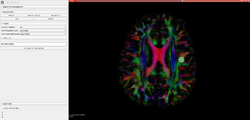

- Diffusion Tensor Image Analysis Along the Perivascular Space (DTI-ALPS): DTI-ALPS Module

- Use Case 1: Obtain the DTI-ALPS index calculation from standard DTI image and propers anatomical labels (see details at <ref>Taoka 2017 paper<\ref>)

- The DTI-ALPS index is a scalar value that represents the activity of the glymphatic system, which may be evaluated with diffusion images. Lower diffusivity along the perivascular space on DTI-APLS seems to reflect impairment of the glymphatic system.